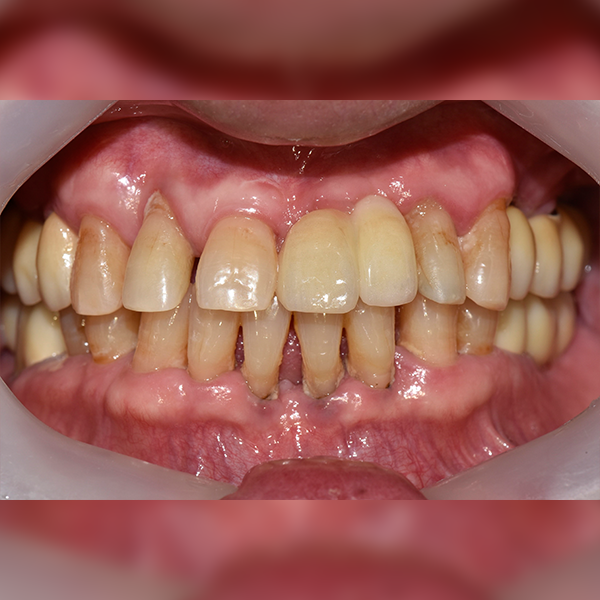

One Day牙科醫院

上顎/前牙部位 / 3顆以下 / 補骨|舒眠|高血壓|糖尿病|阿斯匹靈

案例121 50多歲 黃*元 2018-06-12 / 2019-01-15